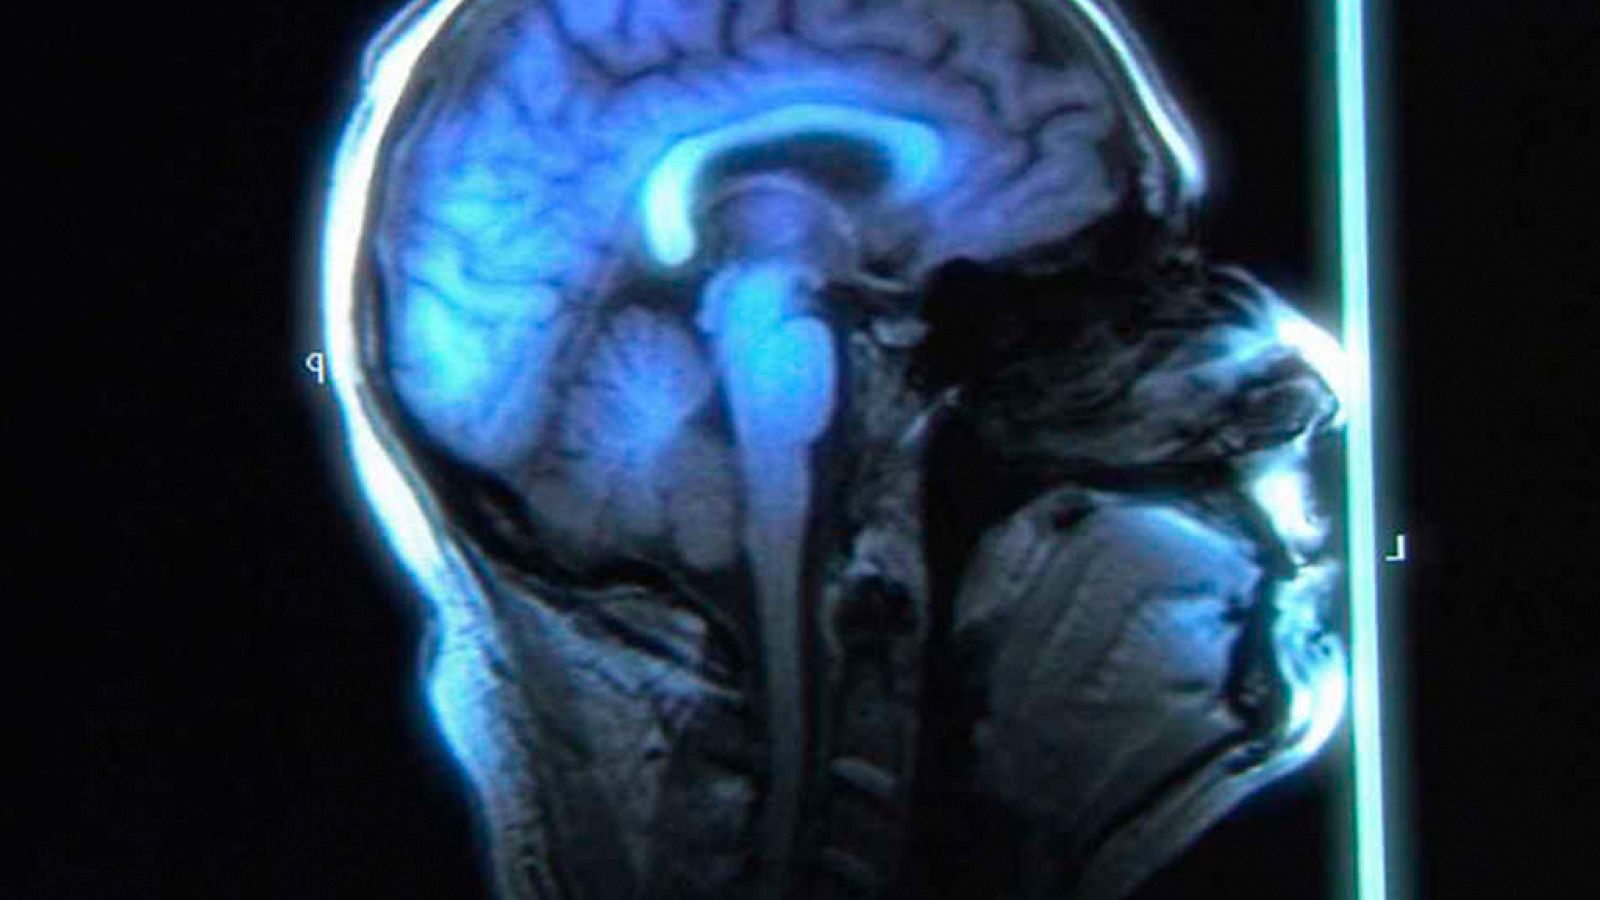

La plasticidad del cerebro. Cambia tu mente

El descubrimiento de la neuroplasticidad ha revolucionado la manera de entender el cerebro y ha abierto la puerta a nuevos tratamientos para...